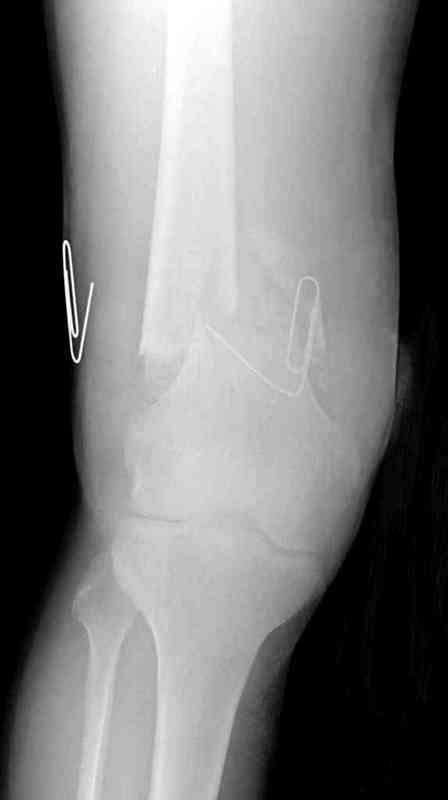

Больная К. с тугим ложным суставом н/3 бедра. Травма в 2005 г.-закрытый перелом, остеосинтез в аппарате Илизарова. В 2006 г. оперирована по поводу несросшегося перелома.

В ноябре 2006 г. демонтаж аппарата, после чего в течении месяца развилась вальгусная деформация. Имеется патологическая подвижность. Объем движений в коленном суставе 180-140. На обсуждение выносятся варианты лечения погружными конструкциями.

The patient with non-union of the distal femur. Trauma in 2005 - closed fracture of the femur, external fixation with Ilizarov apparatus. Non-union. In 2006 open reduction and external fixation with Ilizarov apparatus. In November 2006 the apparatus was removed, after that valgus deformation developed. There is pathological mobility. The knee motion 180-140. We'd like to discuss options of internal fixation.

Надо все-таки разобраться, что там местно - по снимку какое-то как будто сращение на ограниченном участке, но, как пишут, есть и патологическая подвиижность...

Если там сращние или тугой ожный сустав - можно лечить закрыто. Подправить аппаратом и либо заштифтовать, либо пластинку, можно с пластикой, Если дело ближе к болтающемуся ложному суставу - тогда открытая адаптация, аутопластика, как Михаил написал.

Согласен. По снимкам не похоже, чтоб сильно болталось, скорее даже срослось. Клинически с таким коротким фрагментом трудно оценить где "болтается" - в переломе или в суставе. Эффективно смотреть под ЭОПом в режиме скопии.

На мой взгляд, морфологичеескую сущность ложного сустава более объективно отражают данные инструментальных исследований (рентренография, кт, тепловизор, сцинтиграфия), чем физикальные (степень патологической подвижности), по крайней мере данные рг предоставлены - отсутствует периостальная реакция, начинающееся сглаживание концов отломков, склерозированная зона "сращения на ограниченном участке" скорее всего свидетельствуют о редукции кровоснабжения данной области и о формировании атрофического ложного сустава.